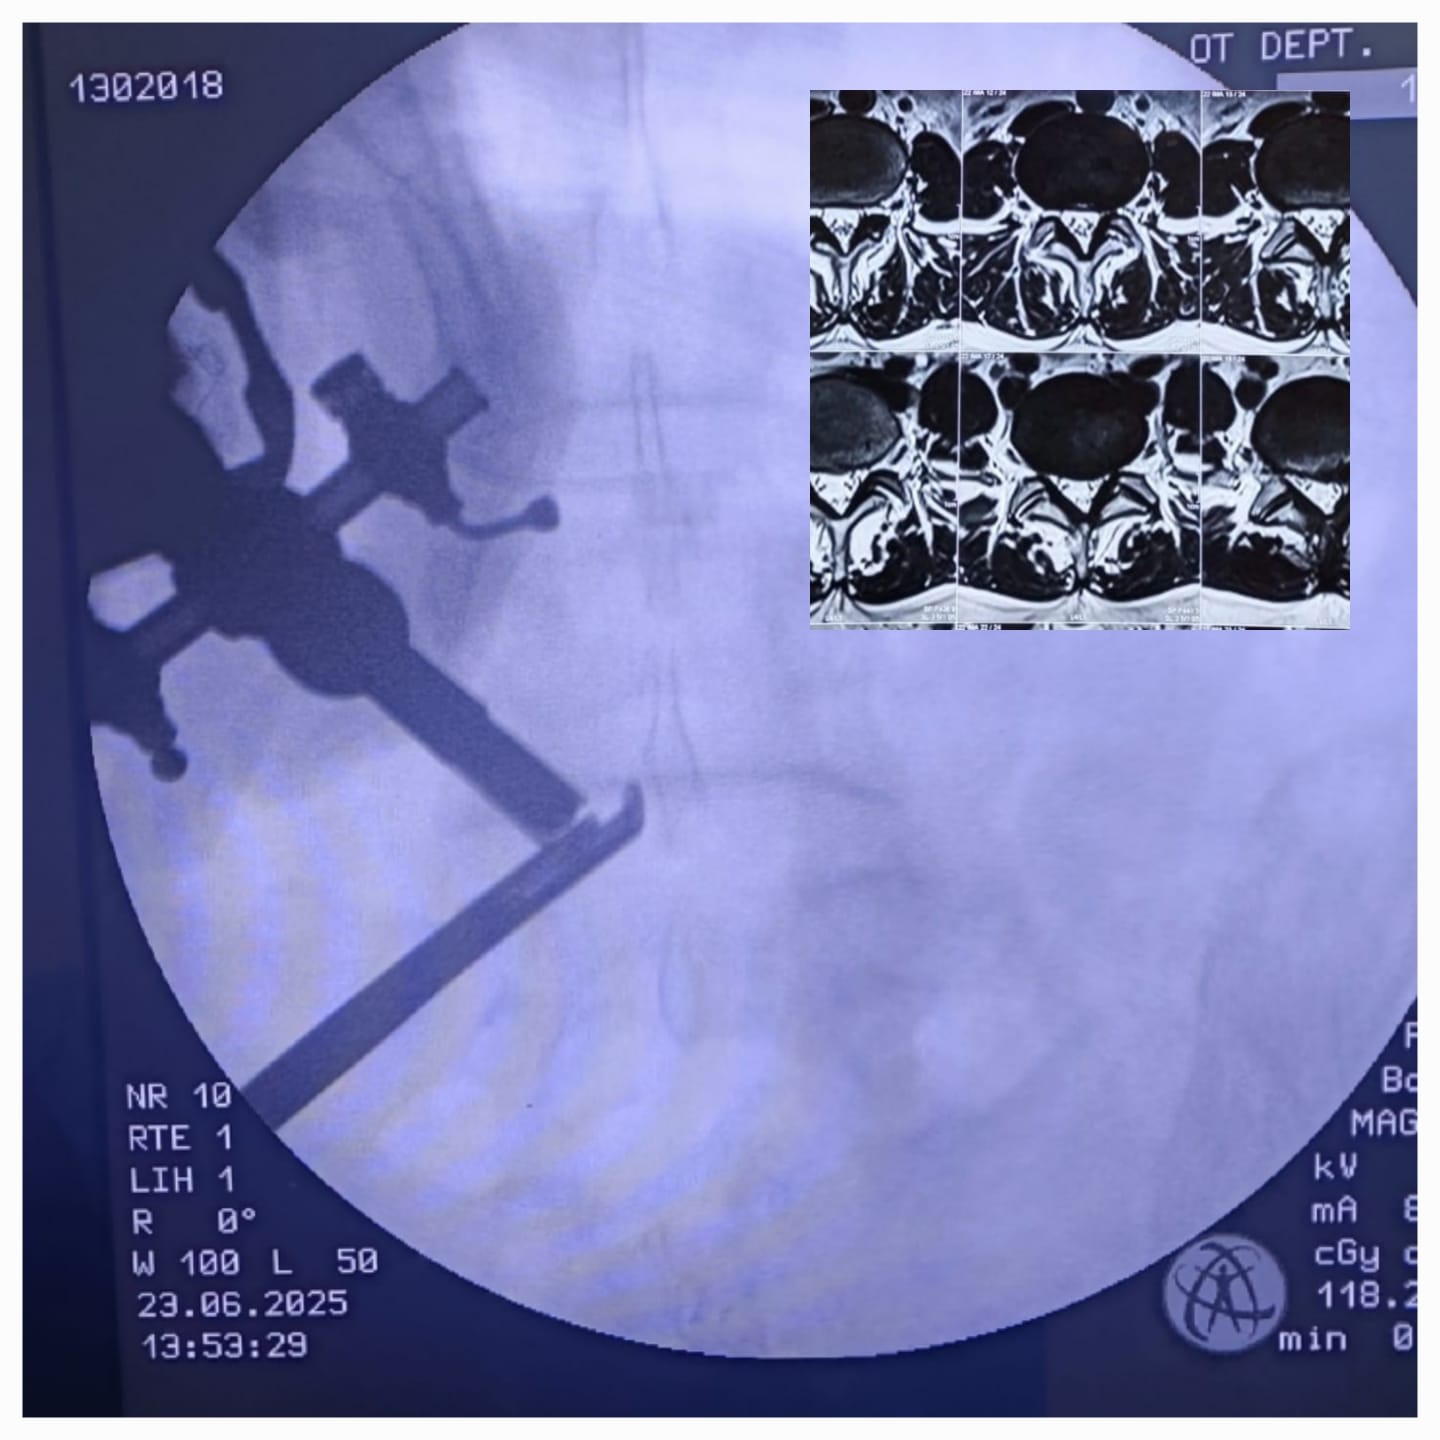

MRI scans showed lateral recess stenosis at the L4-L5 level, a narrowing of the space around the nerve root, leading to compression of the nerve and causing her symptoms.

• Minimally invasive Endoscopic Spine Surgery (UBE technique)

• Lateral recess decompression and mobilisation of the compressed nerve root